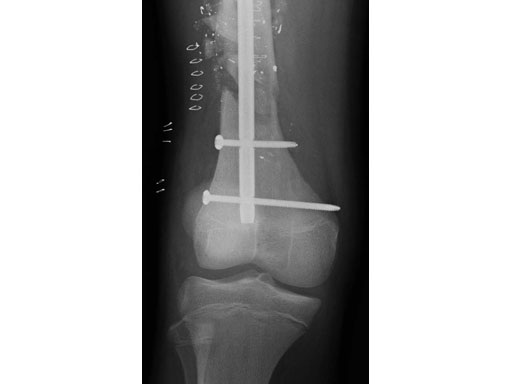

After stabilizing the fracture with an intramedullary nail (Fig 2) the patient was mobilized with weight bearing as tolerated. Uneventful healing and range of motion of the knee and functional ambulation returned to normal. Alignment of the fracture has been maintained with healing and maturation of callus processing as predicted. Blood supply to the proximal femur has been reserved with no signs of avascular necrosis. The ALFN's lateral entry point makes the nail insertion safer and diminishes the risk of circumflex artery injury.

Fig 2 Immediate postoperative AP x-ray.